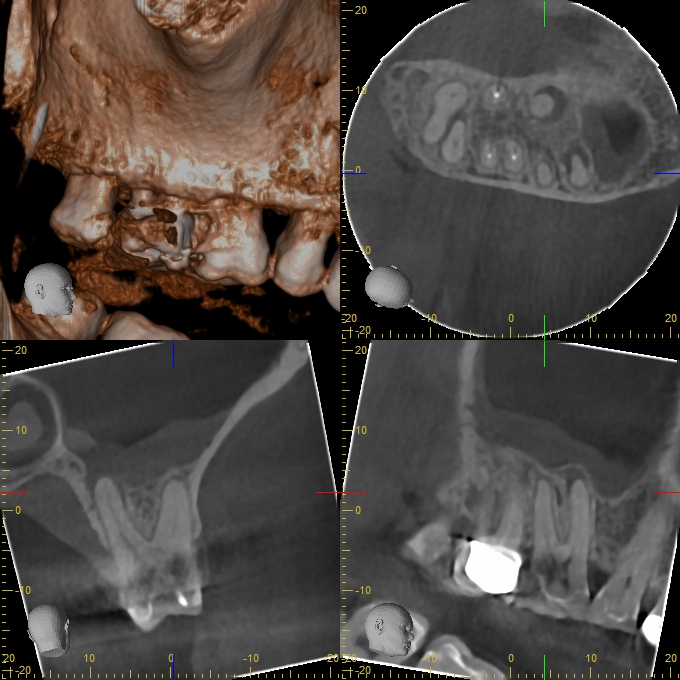

XYZView_20140429_111902

680 × 680

2D vs. 3D (XXVII)